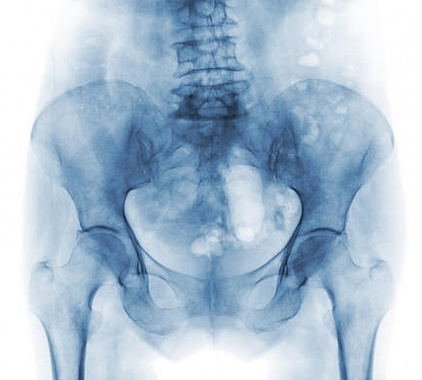

Фотогалерея

Рентген-аппарат